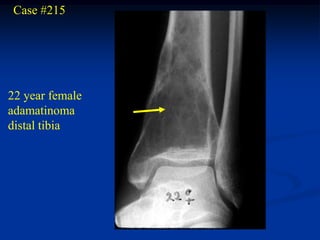

Case #215

22 year female

adamatinoma

distal tibia